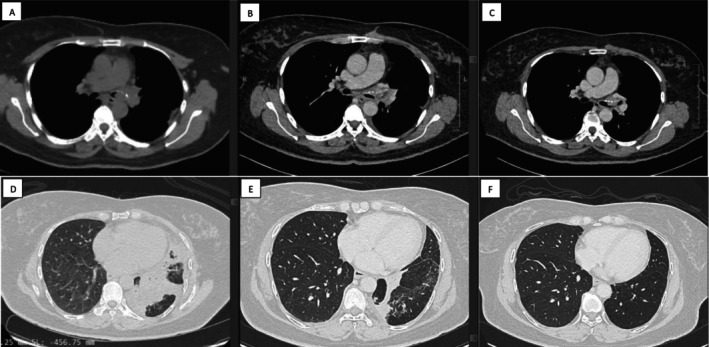

肺腺样囊性癌(PACC)是一种罕见的气管支气管树涎腺型恶性肿瘤,占原发性肺癌的0.04% ~ 0.2%。它可能导致严重的恶性气道阻塞(SMAO),需要紧急干预。手术切除仍然是主要的治疗方法,但不操作性或患者偏好可能需要其他策略。我们报告一例57岁非吸烟女性PACC-SMAO患者,由于左主支气管(LMB)受累而表现为左肺全萎。她拒绝手术,接受了支气管镜双重减压联合电灼术和肿瘤内反复注射对甲苯磺酰胺(PTS)。干预安全地减少了肿瘤负担,恢复了气道通畅,并显著改善了临床和放射预后,无不良事件。我们的病例强调PTS作为一种有希望的辅助治疗不能手术的PACC-SMAO,值得进一步研究其长期疗效和最佳剂量。这种创新的方法可能会大大重新定义姑息治疗的选择。

Pulmonary adenoid cystic carcinoma (PACC) is a rare salivary gland-type malignancy of the tracheobronchial tree, accounting for 0.04%-0.2% of primary lung cancers. It may cause severe malignant airway obstruction (SMAO), necessitating urgent intervention. Surgical resection remains the primary treatment, but inoperability or patient preference may require alternative strategies. We report a case of a 57-year-old non-smoking female with PACC-SMAO who presented with total left lung collapse due to left main bronchus (LMB) involvement. She declined surgery and underwent bronchoscopic dual debulking combining electrocautery snaring with repeated intratumoural para-toluenesulfonamide (PTS) injections. The intervention safely reduced tumour burden, restored airway patency, and significantly improved clinical and radiological outcomes without adverse events. Our case underscores PTS as a promising adjunct therapy for inoperable PACC-SMAO, warranting further investigation into its long-term efficacy and optimal dosing. This innovative approach may significantly redefine palliative care options.